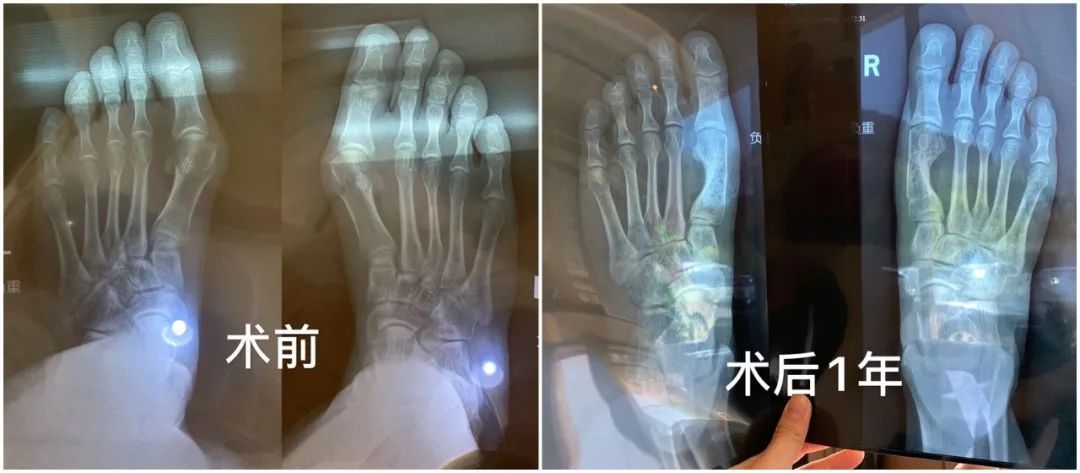

还有每次写高跟鞋都会有人烦恼的问题——拇指外翻。也有小伙伴去做了修复手术,来看看她的分享:

拇指外翻手术

👧🏻X

拇外翻手术

其实拇外翻是一种疾病,所以算是治疗手术,它是可以医保报销的!不算美容!

很多人以为拇外翻只是脚丑,我去年疼痛剧烈,甚至无法走路,立刻在网上找到一位非常合适的三甲医生立刻就做了。传统方式,断骨重接,并不是单纯切掉歪出来的那一块然后掰脚趾头!拇外翻一定不能做微创!一定不能!谁做谁后悔!

住院三天,术后可以脚后跟点地去厕所,卧床到下地一个月,三个月可以恢复剧烈运动。现在不疼不歪不丑,穿鞋美美的了!

医保前23000,医保后8700。我选择了可吸收钉,强度不如钛钉但没有内固定物,几年以后就被人体吸收没了。钛钉强度高,下地时间早,但总归是脚里有个钉子不是。

皮肤疤痕恢复时间因人而异了,有人3个月就看不到了,有人几年还有增生,但疤痕相对拇外翻的问题来说都是小问题了,疤痕在侧面,基本看不到。全部注意事项就是遵医嘱!